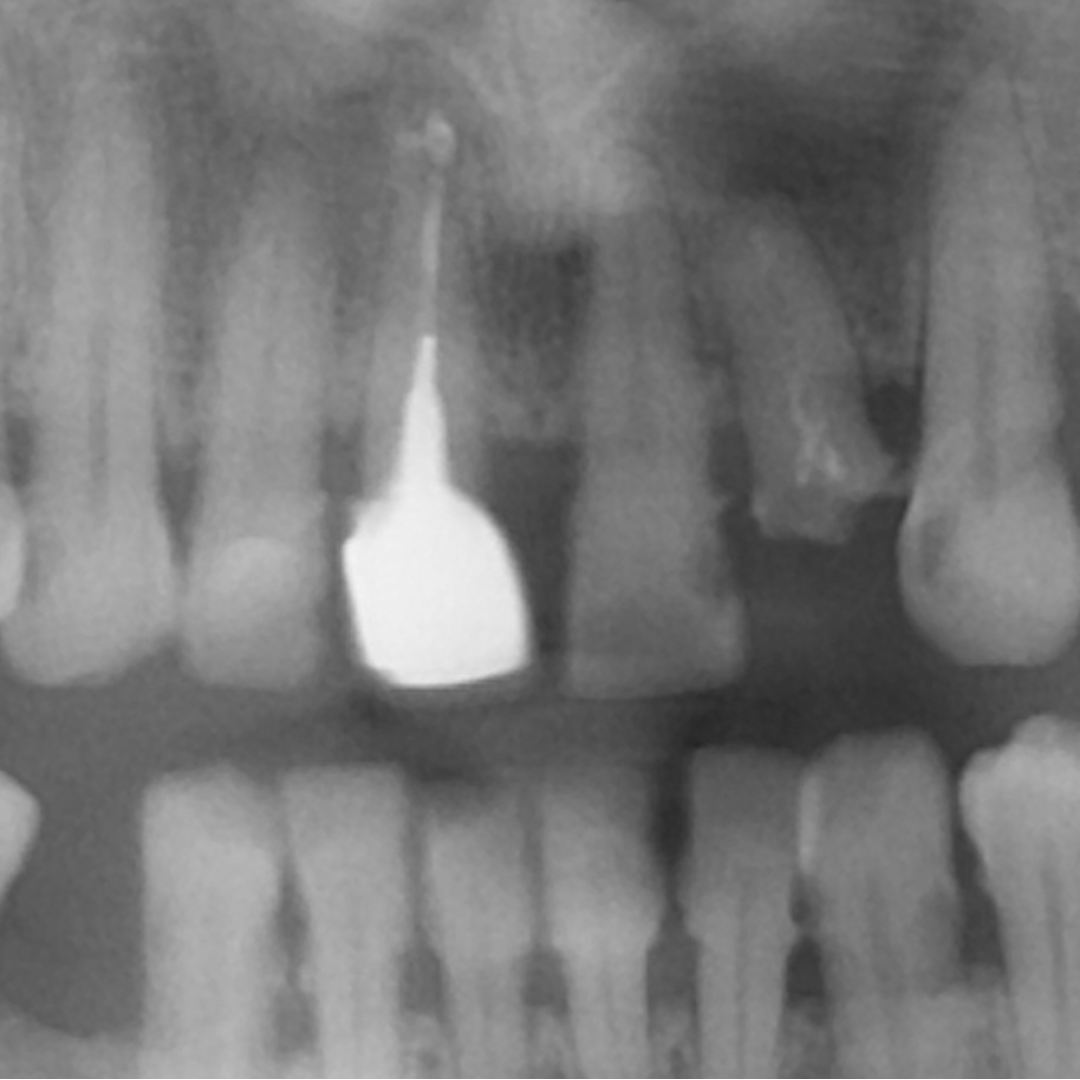

Aspectul radiologic dupa tratamentul de canal, inserarea pivotului si cimentarea coroanei definitive.